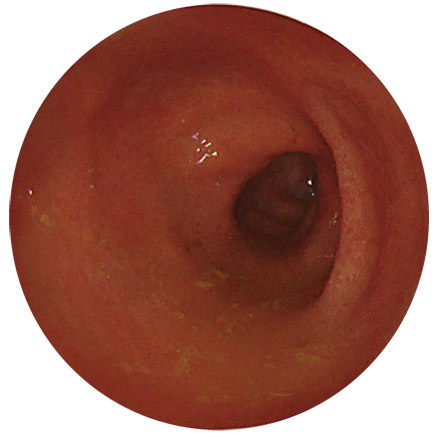

これらの病気を判別するのに必要な検査が、大腸内視鏡検査(大腸カメラ)になります。

大腸がんのでき始めは、一般的にはポリープ(おでき、いぼのようなもの)の形をしており、当院では、大腸カメラを行ったその場で検査と同時に切除することができます。